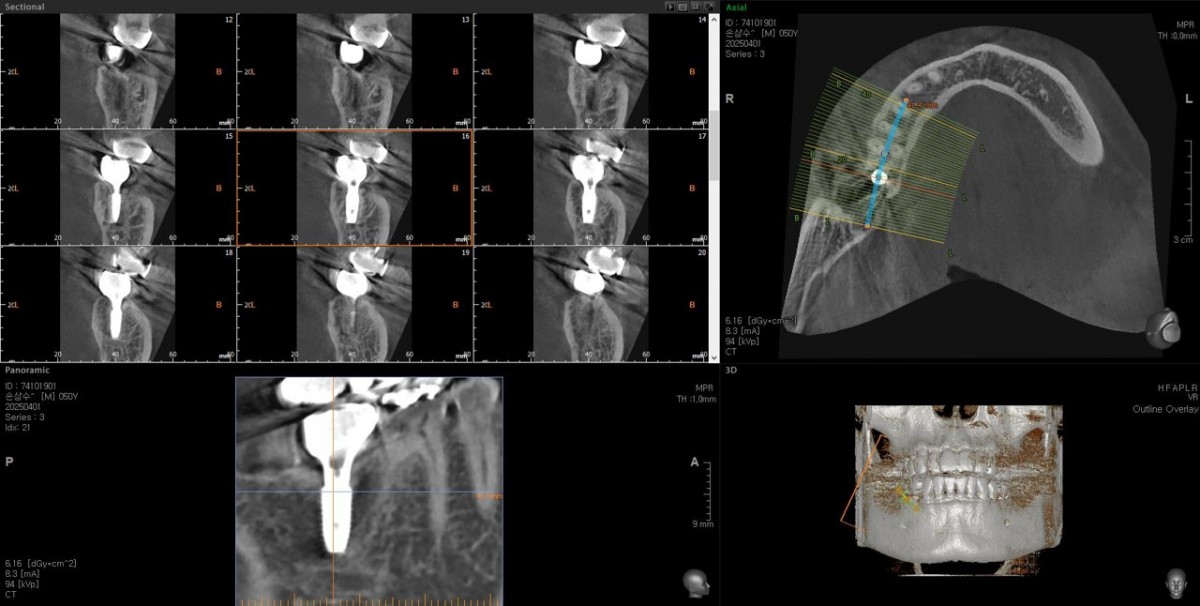

Single implant (staged) Arum NB1, f/u

A 47-year-old male patient had a crown with an ill-fitting margin and crack-tooth syndrome in the lower 2nd molar. No systemic issue.

▲Arum Dentistry NB1 5*10